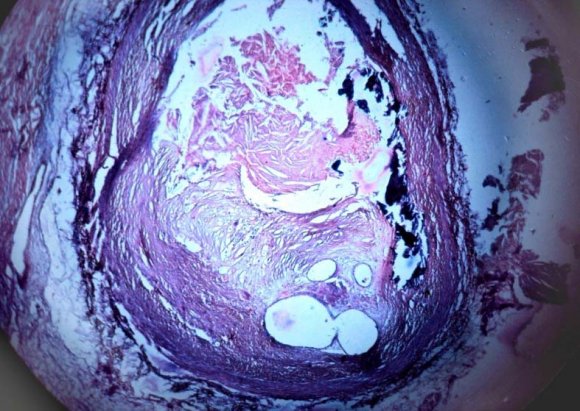

The methods used for the analysis of the material was as per the procedure recommended by 1. White, Edward and Dry (1950). 2. Gore and Tejada (1957). All autopsies were carried out within four to twenty four hours after death. 10,11,12 All the specimens of right and left coronary arteries blocks were taken at a particular fixed distance at from 1.5 cm and 3 cm from the Ostia, also From the circumflex branch of the left coronary artery, bits were taken at the same distance form the point of branching of the left coronary artery into anterior descending and circumflex branches. Additional bits of tissue were taken from other regions of the vessels which showed stenosis. This stenosis is graded based on the luminal narrowing of the coronaries when examined by hand lens and is graded from grade 0 (no narrowing / normal) to grade IV (complete obliteration). Grade -0 : Normal Grade -I : 1-25% stenosis Grade -II : 26-50% stenosis Grade -II : 51-75% stenosis Grade -IV : 76-100% stenosis The bits of the tissue were fixed in 10% formalin and embedded in paraffin. Sections for histological study were taken from the paraffin blocks and stained with haematoxylin and eosin. Special stains were also done whenever indicated, namely Verhoeff and Van-Gieson's for demonstration of elastic tissues, smooth muscle and collagen, and Alcain blue for the demonstration of mucopolysaccharide ground substance. All histological sections were studied for microscopic evidence of atherosclerotic lesions.

Of the 50 heart specimens studied 33 showed coronary atherosclerosis with various histological changes such as fibroblastic activity, mucopolysaccharide deposition, degeneration of internal elastic lamina, accumulation of lipid cholesterol crystals, hyalinization, calcification and hemorrhage. Salient features of atherosclerotic lesions i.

Fatty streaks. ii.

Fibrous plaques. iii.

Atheroma. Histological, examination of representative plaques in the second and third decades showed the presence of fat with little or no cellular reaction. In the 4 th and 5 th decades, there was generally a fibrous tissue reaction to the presence of fat. By the 5 th decade, the fibrous reaction had become more pronounced and was associated with degenerative changes.